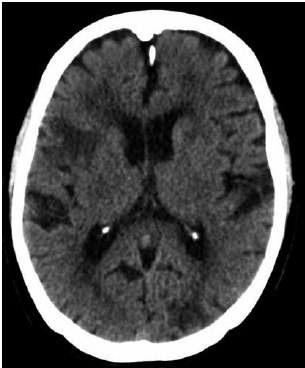

A paciente realizou uma tomografia computadorizada de crânio.

(Arquivo pessoal; imagem usada com autorização)